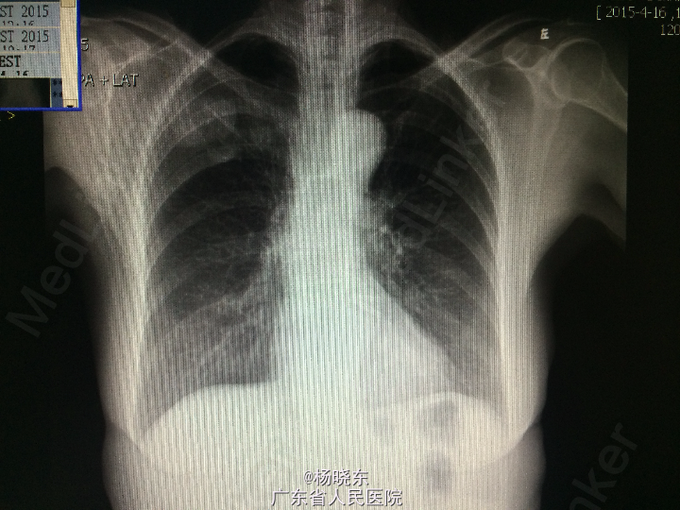

主诉:反复胸背痛1年,加重1月。 病史:患者1年前无明显诱因出现右侧胸背痛,性质为隐痛,无向周围放射。遂至当地医院门诊就诊,查胸部CT,考虑“胸膜肿瘤”,建议手术处理,但患者拒绝未予治疗,症状持续数天后自行消失。后间断出现类似症状,但均可忍耐。1月前患者自觉右上肢上抬及抬举重物时右侧胸背痛明显,不伴有其余部位牵涉痛,未予重视。近1周来,患者自觉症状加重,疼痛致右上肢不可上抬,弯腰时加重,平卧时可缓解。现为进一步手术治疗入院,无发热,无头晕、头痛,无咳嗽、咳痰,无气促、心悸,无恶心、呕吐,无腹痛、腹泻,无皮疹、无双下肢浮肿。自起病以来,精神、睡眠可,食欲可,二便正常,体重近1月下降2kg。

查体:右侧胸肋部及肩胛区压痛明显。 辅查:胸片,CT。

诊断:胸膜间皮瘤 处理:右侧胸膜肿瘤切除术